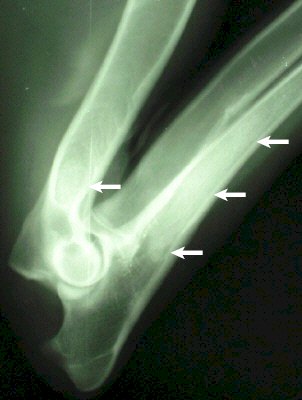

Röntgenbild: rechter Oberarm - Ellbogen - Leonberger, 5 Monate

hochgradige Panostitis mit wolkigen Verschattungen